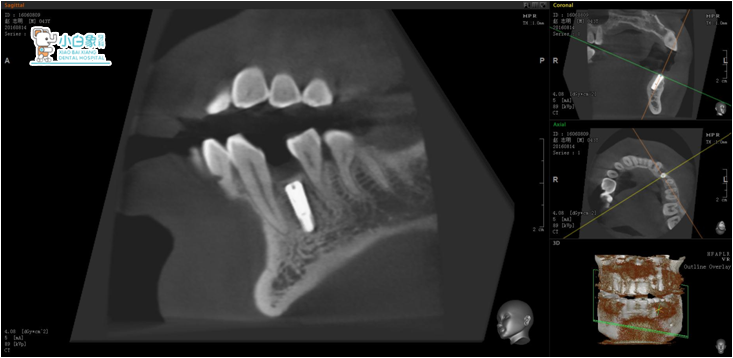

图片4

图片5

2017年3月3日   34硅橡胶取模

图片6

基台+戴牙